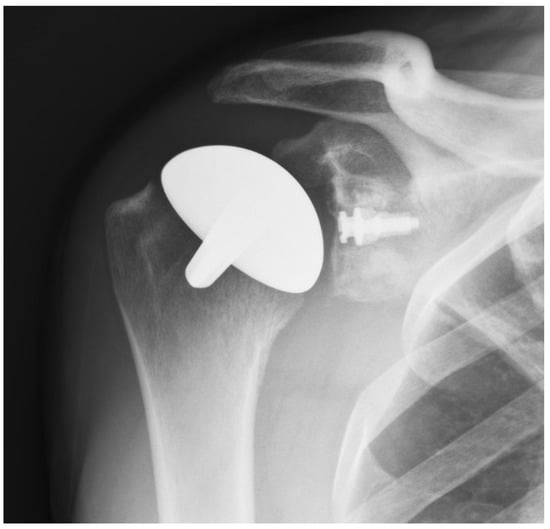

In the majority of cases, the humeral resurfacing prosthesis will articulate directly with the preserved glenoid cartilage [8,9,10,11,12,13,14,15]. Therefore, the smoothest possible surface is necessary. Ceramic coating the implant is the best method to achieve this goal (Figure 1).

Figure 1.

Cementless, ceramic-coated shoulder resurfacing implant.